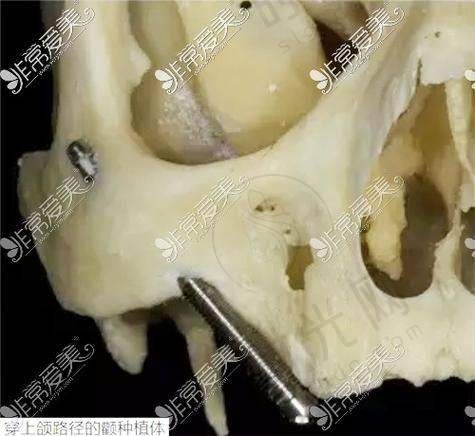

最近的牙科医院技术实力,直接决定治疗成效和使用寿命。以种植牙为例,上海鼎植口腔(陆家嘴1088店)的VIIV穿颧穿翼技术能解决“牙床骨头少”的难题,适合牙槽骨吸收重度的中老年人,而普通社区医院可能只能做简单的即刻种植,术后使用年限相差10年以上。再看正畸,北京劲松口腔望京分院的数字化正畸方案,通过3D打印托槽实现矫正周期缩短2个月,比100米外的小诊所效率提升40%。

1. 种植牙:优先选有“穿颧穿翼技术”或“数字化导板种植”的医院,比如上海维乐口腔的VIIV技术,能减少手术创伤,术后当天就能进食;

实例:58岁的刘先生在小区门口诊所种牙失败,原因是医生没发现他的牙槽骨密度不足。后来到1公里外的上海鼎植口腔,医生用VIIV穿翼技术避开骨量不足区域,手术时间仅40分钟,现在用了3年吃饭和真牙一样有劲。这说明技术选对了,稍微远一点也值得。